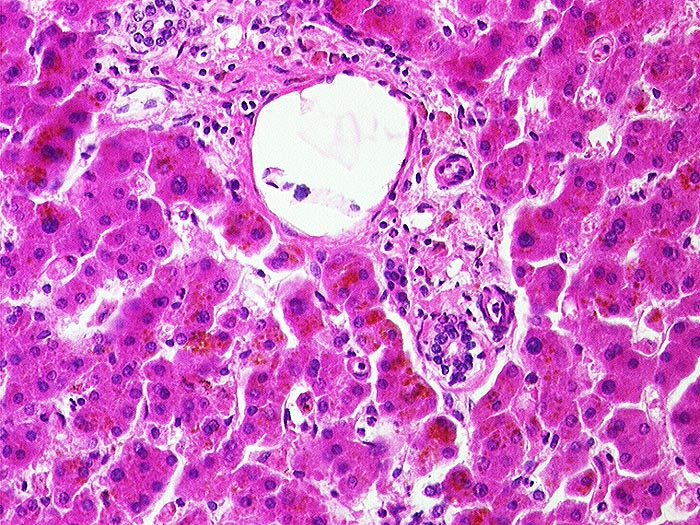

PathoPic – image database / PathoPic ID 1265 - Lipofuszinose bei Phenacetinabusus

Lipofuszinose bei Phenacetinabusus

Artefakt / Fremdkörper / Pigment

Leber

Braunes Pigment in den Hepatozyten.

Diffuse Ablagerungen von Lipofuszinpigment in der Leber.

Phenacetinabusus.

Lipofuscinpigment kommt auch unabhängig von Phenacetinabusus im Alter vor. Makroskopisch braune Atrophie der Leber.

Histologie